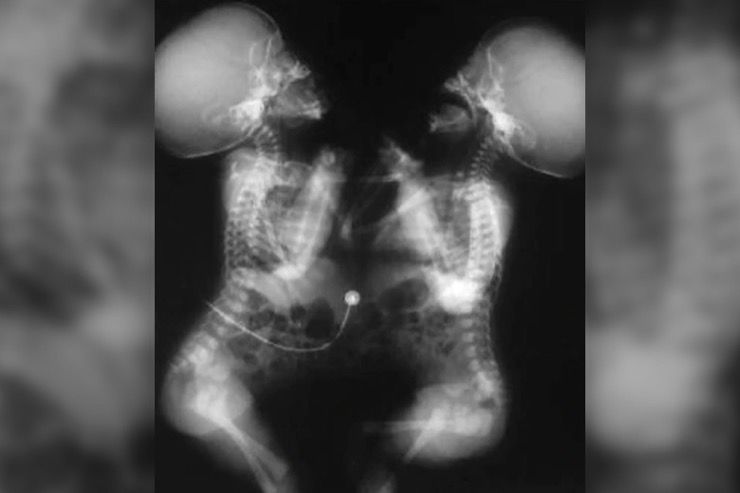

When Nima and Dawa were born as conjoined twins, connected by their lower chest and through their tummies, their mother Bhumchu Zangmo knew that life would be a struggle for them as well as for the whole family for years to come.

For Crameri, the procedure can be successful in separating the twins without leaving any “long-term legacies.” “We think they have joined liver which we can separate; we think they have joined bowel which we can separate; we don’t think they have major structures such as the heart or the lungs which are shared,” he said. “So it also means we have the opportunity to separate them without leaving them with long-term legacies, and I think that is important.”